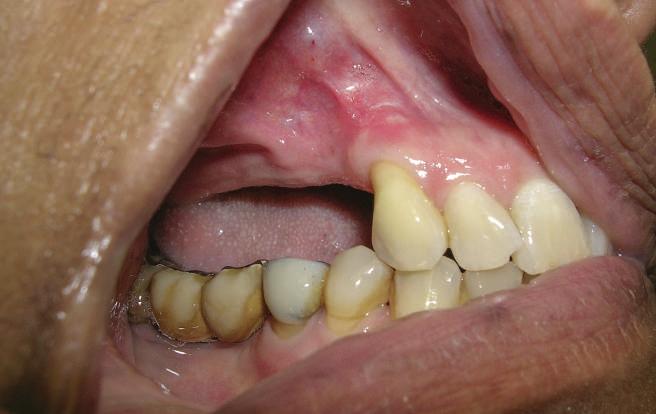

Atitudine: Până la dobândirea vindecării totale a ţesuturilor şi a implanturilor secundare s-au utilizat bonturi standard de titan. Fig. 18 prezintă bonturile individualizate maxilare şi mandibulare aplicate iar fig. 19 un prim-plan al cadranelor de partea dreaptă a pacientului, afişând finalizarea cazului la 15 luni după începerea tratamentului iniţial. Recesiile se pot obiectiva corespunzător 1.4. şi 1.3. În acest caz, s-a încercat minimizarea susceptibilităţii la recesie prin implicarea bonturilor temporare standard fixate cu şurub în cursul fazelor de vindecare pe toată durata etapelor iniţiale ale tratamentului.

În pofida acestor eforturi, totuşi, recesia a apărut în anumite regiuni unde implanturile erau plasate vestibular. Ulterior, s-a încercat grefarea ţesutui moale din jurul locaţiilor cu recesie, dar fără succes.

Rezultatul final al cazului 5 (fig. 19) prezintă recesie vestibulară de peste 2mm în jurul bonturilor cu sprijin implantar, fiind evidentă prezenţa unui ţesut moale foarte redus din cauza plasării vestibulare a implanturilor. Butler, Kinzer susţin premiza că trebuie să existe suficient volum osos vestibular, chiar şi atunci când implantul este plasat ideal, multe complicaţii fiind legate mai degrabă de poziţia implantului.

Cazul (5):

Bonturi conice utilizate ca bonturi temporare

Figurile

16, 17. Implanturile din prima etapă încărcate cu bonturi conice şi, în unele cazuri, omologii angulaţi.

18. Bonturile individualizate inserate.

19. Rezultat final la 15 luni după începerea tratamentului iniţial.

şi va induce resorbţie osoasă şi migraţia apicală a ţesutului (Saadoun & Touati). Dacă implantul nu este plasat mai palatinal şi la 3-4mm apical de marginea gingivală liberă pentru a asigura profilul de emergenţă adecvat, rezultatul estetic este compromis (Chu et al). Un studiu de 2 ani a demonstrat că implanturile poziţionate anterior au demonstrat o recesie uşor mai accentuată, decât implanturile posterioare (Bengazi et al). Plasarea vestibulară a implanturilor se poate vizualiza clar în cazul 5 (fig. 17) cu bonturile de vindecare în poziţie.

Proximitatea implanturilor adiacente

Se recomandă existenţa a cel puţin 3mm de os între două implanturi adiacente (Tarnow et al). În acelaşi caz 5, corespunzător 2.5. şi 2.6. distanţa la nivel inter-implantar este sub 2mm iar între bonturi sub 1mm (fig. 17). Întrucât ţesuturile inter-implantare nu au acelaşi nivel de suport ca în cazul dinţilor naturali, distanţa interdentară devine esenţială în anticiparea poziţiilor finale ale ţesutului moale.